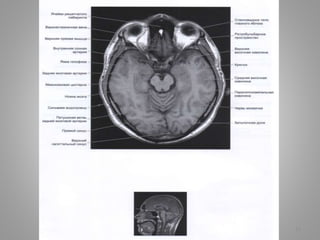

Великі цистерни головного мозку

• Велика (мозочково-мозкова) цистерна (cisterna magna, c. cerebellomedullaris) –

• Цистерна моста (препонтинна) - розташовується наперед від моста мозку, містить

базилярну артерію. Зєднується позаду з мосто-мозочково-мозковою цистерною та

субарахноідальним простором спинного мозку, попереду – з міжніжковою

цистрною.

• Базальна цистерна (c. suprasellar) має п'ятикутну форму, включає міжніжкову

цистерну (між ніжками мозку) і цистерну перехреста (між перехрестом зорових

нервів і лобними частками).

• Чотиригорбкова цистерна (вени Галена) (c. quadrigeminalis) розташовується між

мозолистим тілом і мозочком; у її ділянці можуть розташовуватись

субарахноідальні кисти

• Обвідна (охоплююча; по Синельникову - обхідна) цистерна (c. ambient) - канал

неправильної форми, що проходить по бокам ніжок мозку і даху середнього

мозку; сполучається з мостовою і міжніжковою цистернами спереду і

чотирегорбиковою цистерною ззаду.

• Цистерна бічної ямки великого мозку (cisterna fossae lateralis cerebri) -

розташовується в латеральній борозні великого мозку.

9